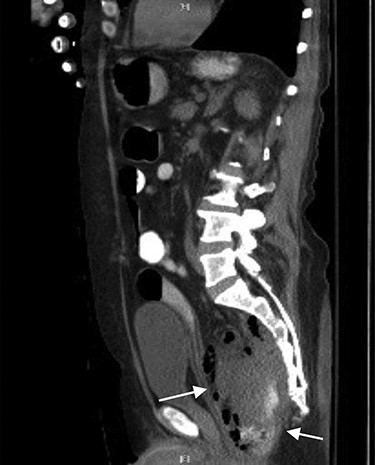

CT abdomen and pelvis showed a rectal perforation with perirectal pelvic inflammatory soft tissue/phlegmon containing air-fluid level that infiltrated into the presacral space extending up through the sciatic notch into the right gluteus medius and minimus muscle (Figs 1 and 2). Chronic inflammatory changes of the transverse colon and left colon were also present. The patient was taken to the operating room (OR) for examination under anesthesia. A flexible sigmoidoscopy was passed up into the distal descending colon, which showed discontinuous areas of ulcerated mucosa with cobble-stoning notable for active Crohn’s disease and a diffuse pseudomembrane reminiscent of C. difficile colitis (the negative C. difficle assay). A rectal perforation was noted just above the dentate line. The incision was enlarged and the presacral space was entered with a flexible sigmoidoscope. There was extensive necrosis of the presacral tissue with copious amounts of purulent fluid. The abscess was evacuated, and all loculated fluid collections were drained. The cavity was then irrigated via the sigmoidoscope. Once satisfactory drainage was achieved, a Malecot catheter was then inserted through the rectal perforation into the presacral space. A laparoscopic diverting loop ileostomy was then created to allow for healing.

CT axial view showing tract from presacral space through the sciatic notch to thigh muscles.